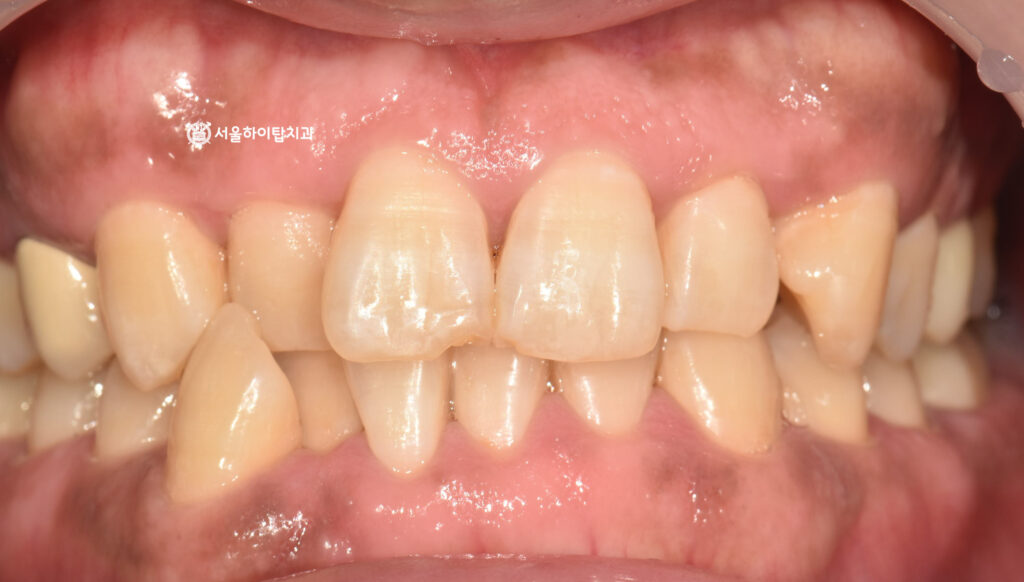

초진 – 파절된 절단연

26.02.06

십정동 치과 에서 준비한 구강 사진을 확인해 보면,

앞니에서 파절된 형태가 뚜렷하게 관찰됩니다.

특히 파절이 발생한 부위가 절단연 부위라는 점도

사진을 통해 비교적 쉽게 확인할 수 있습니다.